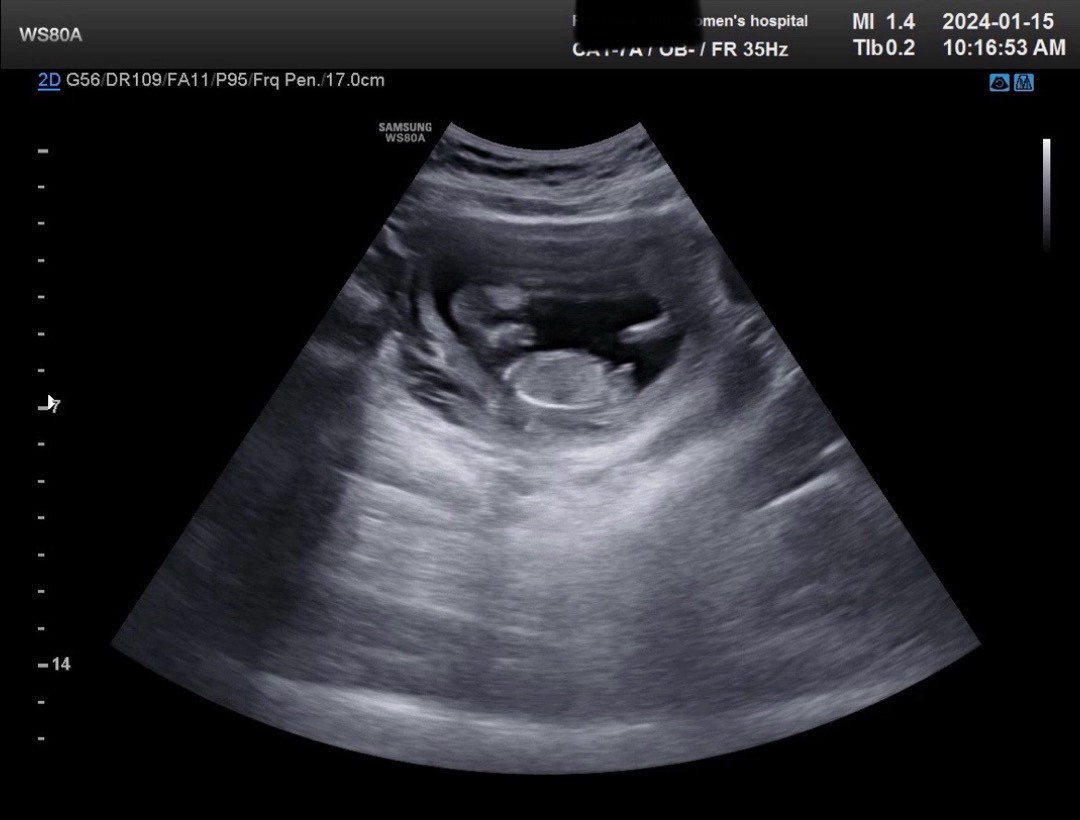

12주1일 아들같다는데 아들 맞을라나요??ㅎㅎ

원장님이 뭐가 보인다고 하시며 아들같다는데 아들 맞을까요?? 제눈에도 보이긴해요ㅋㅋㅋ

저 12주에 아들이라고 하셨다가 15주에 딸로 바꼈어요! 아직 몰라요ㅠㅠㅠㅠ

오 아들 한표요 ㅎㅎㅎ

각도는 아들각도같네용!